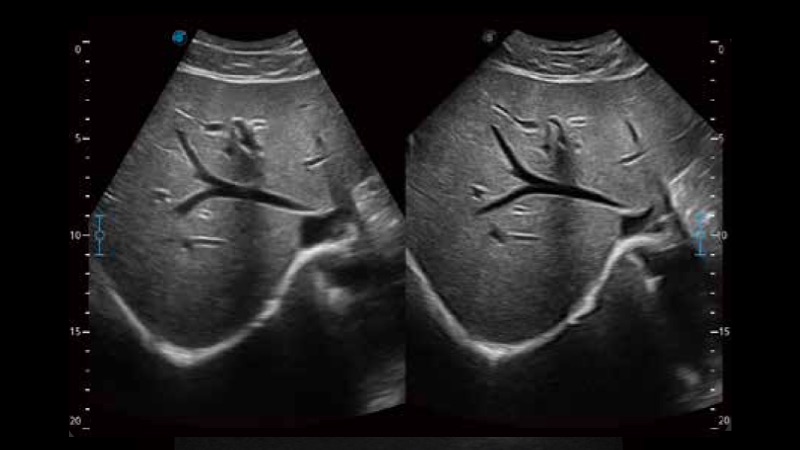

扩展成像技术

凸阵、线阵和相控阵探头进行实时扫描时,开启扩展成像模式,可以扩展超声图像视野,以便更完整地查看大的病灶或组织器官的解剖结构。